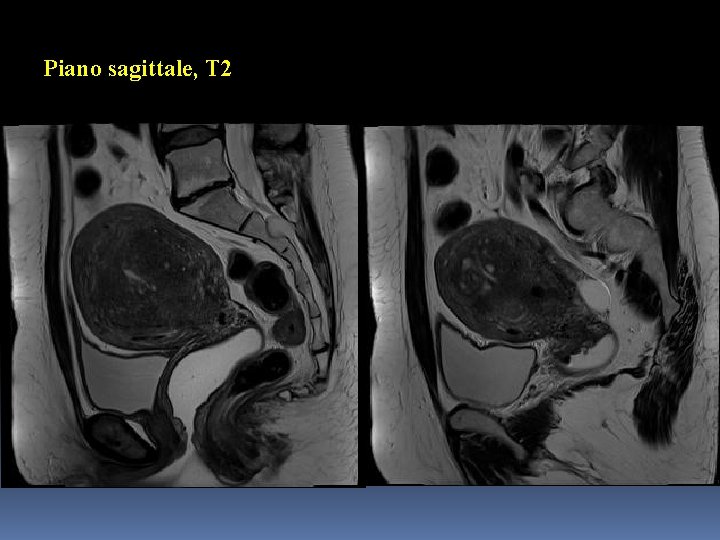

Piano sagittale, T 2

Somiglianze Lesioni di grandi dimensioni → utero ingrandito e globoso Epicentro nel miometrio Segnale prevalentemente ipointenso in T 2 Assenza di grasso endolesionale Comportamento non significativo in DWI/ADC (diffusività non significativamente ristretta, cellularità poco aumentata)

Differenze (1) Interfaccia con il miometrio contiguo/visibilità e caratteristiche dei margini pseudocapsula/margini riconoscibili e netti nel Caso 1 interfaccia mal identificabile/margini sfumati nel Caso 2 Estensione, sede e rapporti anatomici lesione unica (focale) coinvolgente l’intero spessore del miometrio nel Caso 1 processo diffuso coinvolgente la zona giunzionale nel Caso 2

Differenze (2) Segnale in T 2 aree endolesionali modicamente iperintense e a margini non netti nel Caso 1 areole endolesionali iperintense e a margini netti (microcisti) nel Caso 2 Segnale in T 1 Fat sat isointenso con il miometrio nel Caso 1 con isolate areole a contenuto ematico nel Caso 2

Caso 2: immagini-chiave Processo diffuso coinvolgente la zona giunzionale

Caso 2: immagini-chiave Microcisti a margini netti, alcune a contenuto ematico

Caso 2: diagnosi Adenomiosi diffusa in utero arcuato

Adenomiosi Endometriosi: malattia caratterizzata dalla presenza di tessuto endometriale in sede ectopica. Tale tessuto risponde agli stimoli ormonali come quello ortotopico. Adenomiosi: forma particolare di endometriosi in cui l’ectopia si realizza nello spessore della parete uterina (e più precisamente nel miometrio). Tale forma è in genere caratterizzata da un ispessimento dello strato interno del miometrio (zona giunzionale).